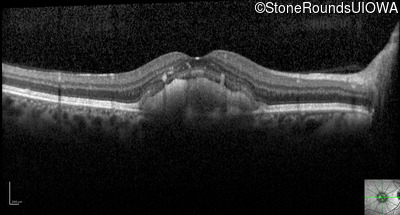

Optical Coherence Tomography - Right - 20/40 -1

Exemplar / OCT Stack